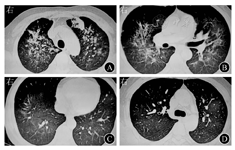

患者男,29岁,体重为52 kg,因"间断腹泻、黏液脓血便半年,拟第3疗程英夫利昔单抗(infliximab,IFX)治疗"于2018年8月20日第2次入住河北医科大学第二医院东院区消化内科。患者半年前出现腹泻、黏液脓血便,每天10余次,2017年12月29日外院电子结肠镜检查示全结肠、直肠黏膜充血水肿、糜烂,多发浅溃疡;乙状结肠黏膜活体组织检查病理结果示黏膜呈急慢性炎症伴炎性渗出,部分腺体轻度异型增生。考虑溃疡性结肠炎(ulcerative colitis,UC),给予患者美沙拉秦肠溶片口服、美沙拉秦灌肠液灌肠治疗,并予注射用甲泼尼龙琥珀酸钠60 mg(1次/d)静脉滴注14 d后改为甲泼尼龙片32 mg(1次/d)口服,症状明显好转,排黄色成形便(1次/d),无脓血,但未复查结肠镜。此后口服甲泼尼龙片,每周减量4 mg,但减量至12 mg/d时再次出现黏液脓血便,7~8次/d。于外院再次静脉滴注注射用甲泼尼龙琥珀酸钠60 mg(1次/d)10 d后,改为口服甲泼尼龙片32 mg(1次/d),症状缓解,但减量至28 mg/d时再次出现黏液脓血便,7~8次/d,遂于2018年6月25日第1次就诊于河北医科大学第二医院东院区消化内科。入院后病毒系列检查:EB病毒9.00×103拷贝数/mL,巨细胞病毒8.49×102拷贝数/mL;粪便艰难梭菌培养:艰难梭菌毒素B阳性。完善结肠镜和病理学等检查后诊断为UC(慢性复发型、广泛结肠型、活动期、重度),巨细胞病毒、EB病毒和艰难梭菌感染。根据患者既往诊疗和病情演变,考虑其存在激素依赖,给予美沙拉秦抑制肠道炎症和抗病毒、抗艰难梭菌等治疗,2018年6月29日胸部计算机断层扫描(computed tomography,CT)检查未见异常。于2018年7月9日、7月23日分别行第1、2疗程IFX治疗,2次剂量均为0.3 g(5.7 mg/kg)。患者症状逐渐好转,每天排1~2次黄色成形便,无黏液和脓血,于2018年8月6日出院。患者出院后约1周即出现咳嗽、咳白色黏液痰、气短症状,痰不易咳出、量少,无发热,症状无加重,未予特殊处理。2018年8月20日第2次入院拟行第3疗程IFX治疗。入院后体格检查:双肺呼吸音粗糙,可闻及散在湿性啰音;腹部平坦,无压痛、反跳痛和肌紧张,肠鸣音无异常。血气分析:pH值为7.37,氧分压为90 mmHg(1 mmHg=0.133 kPa),二氧化碳分压为38 mmHg,剩余碱为1.47 mmol/L;血常规检查:白细胞计数为10.88×109/L,中性粒细胞占比为0.439 0,嗜酸性粒细胞占比为0.025 8,血红蛋白为109 g/L,血小板计数为229×109/L,红细胞沉降率为14 mm/1 h,超敏C反应蛋白为225 mg/L;降钙素原为0.07 g/L;3次粪便细菌涂片和培养均未见异常;肺炎支原体抗体阴性;多次痰真菌、结核分枝杆菌涂片和痰液培养均未见异常;2次γ-干扰素释放试验均为阴性;结核菌素试验阴性;1,3-β-D葡聚糖检测和半乳糖甘露醇聚糖抗原检测均未见异常;2次病毒系列检查均阴性。2018年8月21日胸部CT检查结果与2018年6月29日相比较:双肺血管、支气管树周围出现多发片状和磨玻璃样密度增高影,边缘欠清晰,密度不均,双肺内多发病变,暂考虑多发炎性病变(图1A)。请呼吸科医师会诊协助诊治,同时给予哌拉西林他唑巴坦联合盐酸左氧氟沙星等药物行抗感染治疗2周余,患者咳嗽、咳痰症状无明显缓解,2018年9月9日复查胸部CT亦无明显好转(图1B)。复查血常规示嗜酸性粒细胞占比为0.331 8,嗜酸性粒细胞计数为2.23×109/L;肺功能检查示限制性通气功能轻度下降,弥散功能中度下降。考虑患者无细菌、真菌、支原体等感染证据,抗生素治疗无好转,且出现外周血嗜酸性粒细胞明显升高、肺功能下降,结合病史、用药情况和转归,考虑不除外药物导致嗜酸性粒细胞性肺炎可能,5-氨基水杨酸和IFX均不能除外。停用美沙拉秦口服、灌肠,暂不行第3疗程IFX治疗,并于2018年9月27日加用醋酸泼尼松片40 mg(1次/d)口服,患者气短症状消失,咳嗽、咳痰明显好转。2018年10月7日复查胸部CT提示两肺多发片状、斑片状、条片状病变,范围较前有所缩小,密度较前减低(图1C)。每天排1~2次黄色成形便,无黏液和脓血,无腹痛、发热,无咳嗽、咳痰等不适,遂出院。出院后糖皮质激素逐渐减量,并应用中药控制UC病情。2018年10月26日再次复查胸部CT,提示病变进一步好转(图1D)。

注:CT为计算机断层扫描